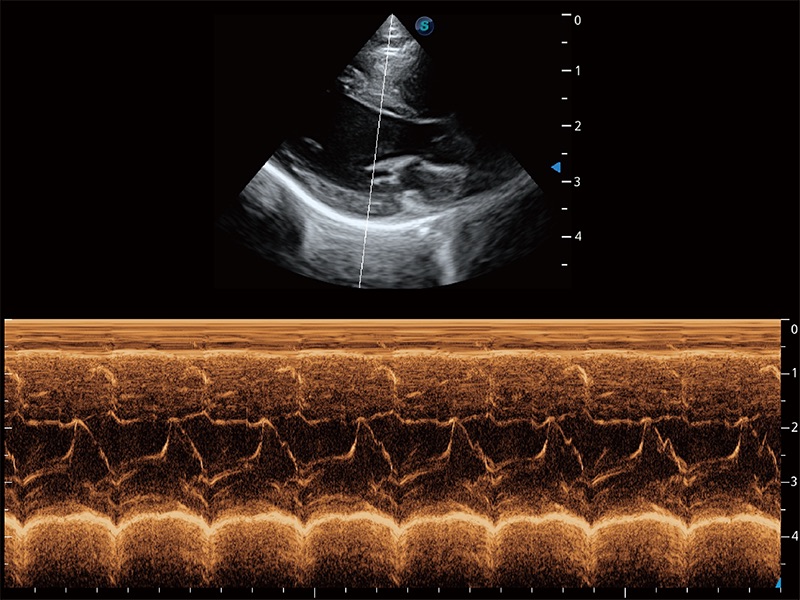

得心應(yīng)手 心臟解決方案

ProPet 80 配備了豐富的心臟探頭群、先進(jìn)的成像技術(shù)和專業(yè)的心臟測量工具,可幫助動物醫(yī)生為不同體型和生理結(jié)構(gòu)的動物提供心臟和心肌功能的全面評估。

• AMM 解剖M型

通過360度任意調(diào)節(jié)3條M型取樣線,在同一心動周期上觀察心臟不同位置的運(yùn)動曲線,得到準(zhǔn)確的心功能測量數(shù)據(jù),有效評估心肌運(yùn)動及左心室功能。

(貓)二尖瓣M型

(犬)二腔心血流